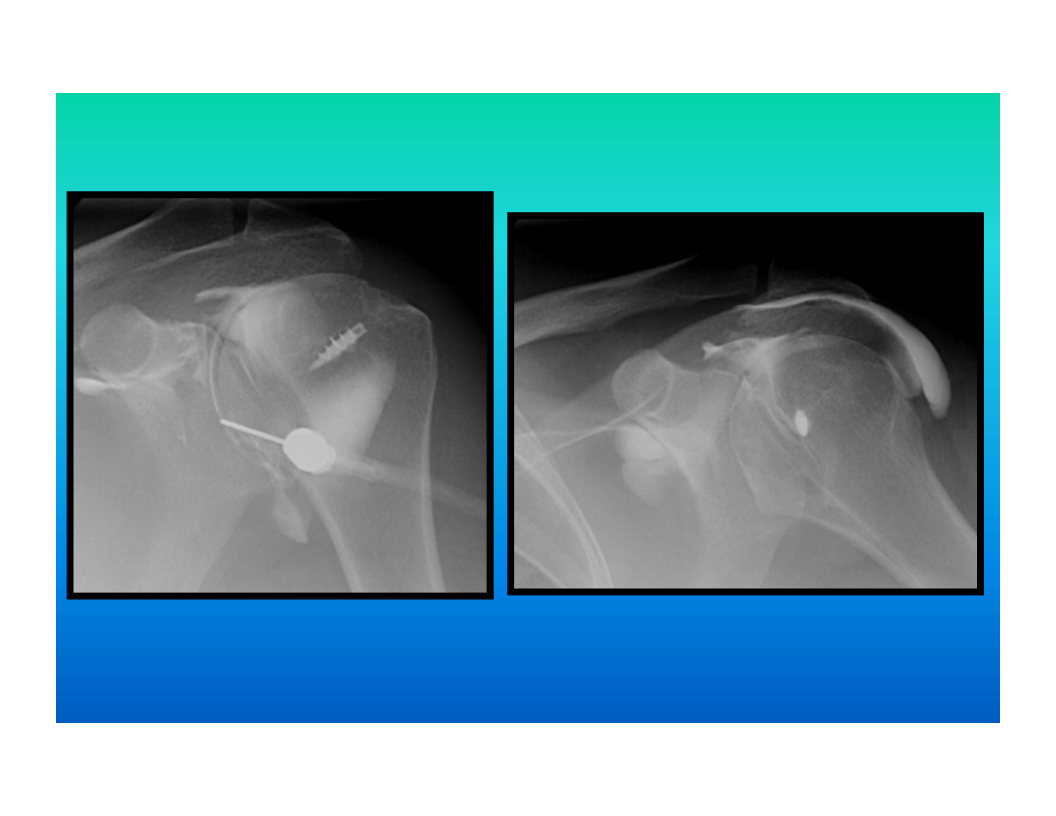

arthrography

injection of contrast and or air into a joint space

can be used to evaluate the shoulder joint as well as the write joint, knee, or ankle